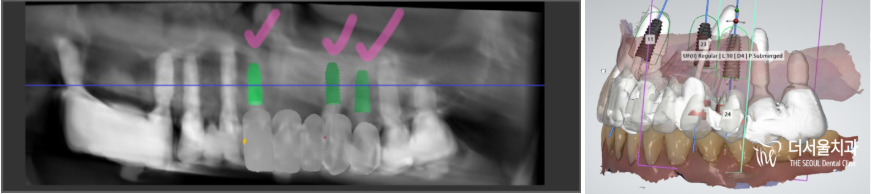

그리고, 이미 하악에는

overdenture 라는 임플란트 에

틀니를 연결해서 쓰는 보철을 끼고 계셨네요.

* 초록색 : 임플란트 수술을 해야 될 곳

* 핑크색 : 틀니를 끼고 있는 곳

먼저 포지션을 설정하며

식립 기울기 및 보철의 형태를 예측합니다.

이어서, 뼈의 단면 및 골질을 파악하며

최선의 결과를 낼 수 있는 위치를 찾는거죠.

표시를 해 둔 곳을 보면

심겨질 implant fixture 의 직경과,

뼈의 두께가 거의 비슷한 것을 볼 수 있죠?

따라서 치조골 이식술 이라 해서

뼈 이식을 하기로 했습니다.